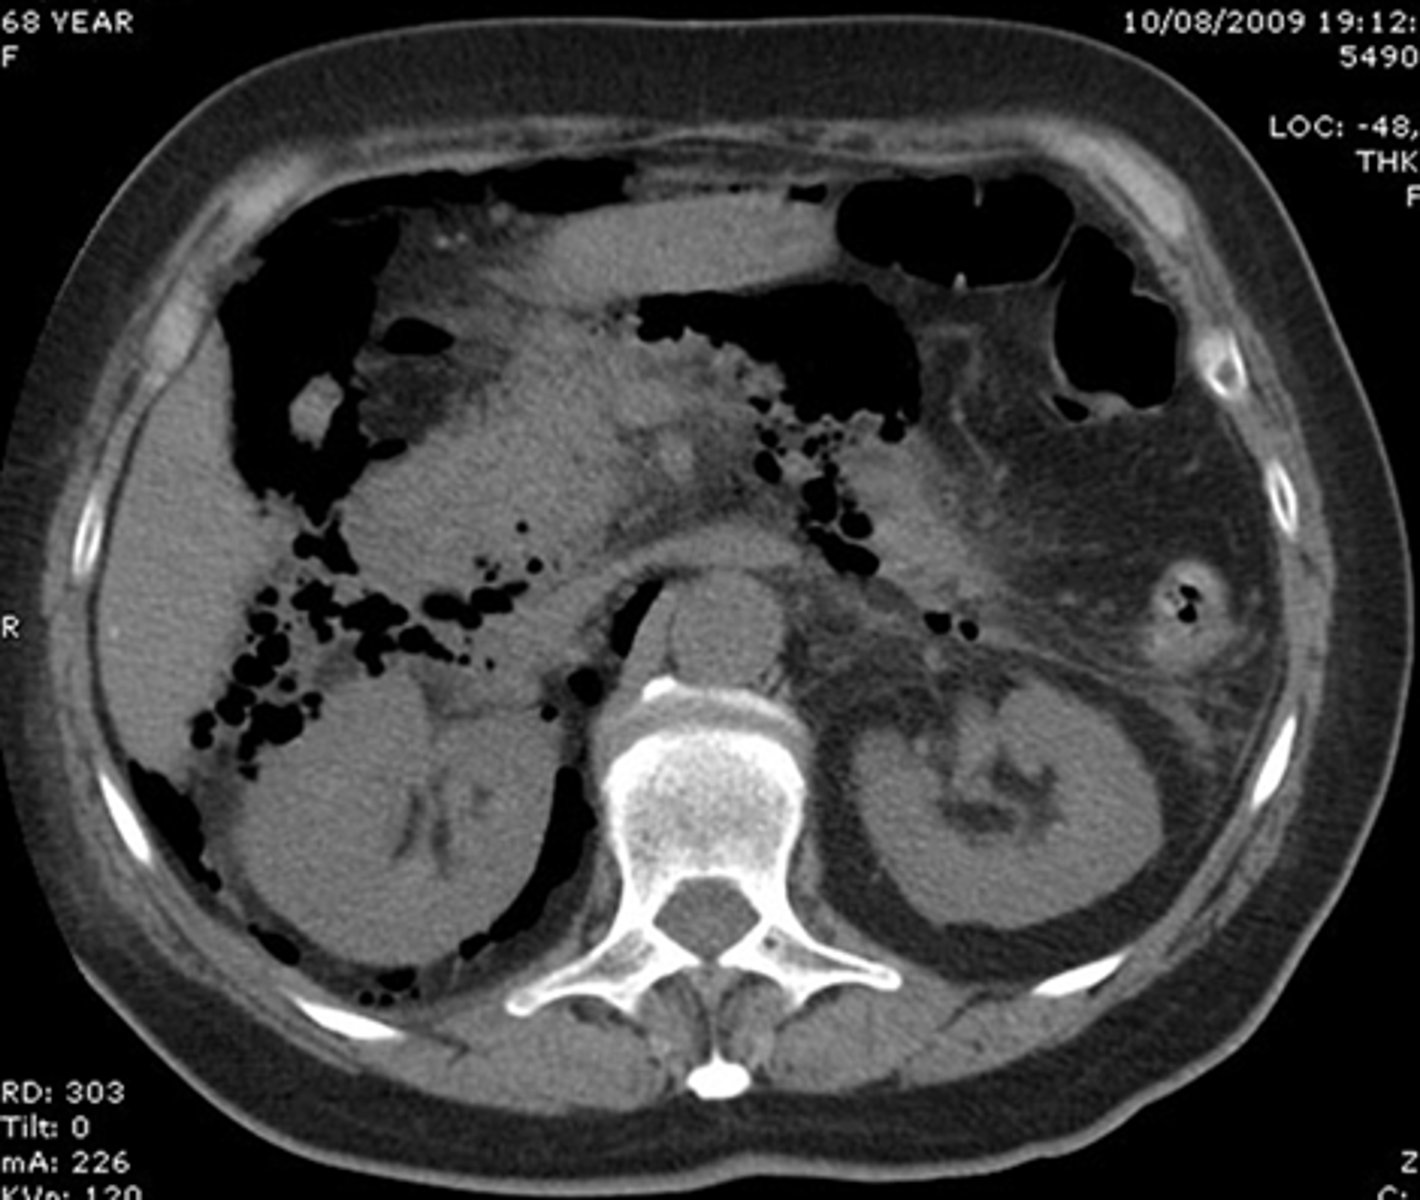

abdominal CT

contrast used with bowel perforations

gastrografin